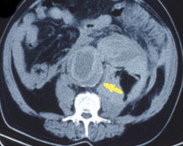

Ruptured Aortic Aneurysm

George Pappas, MD; Nikolaso K. Akritidis, MD; Konstantinos Paparounas, MD, PhD

Severe abdominal pain radiating to the back prompted a 72-year-old man to go to the emergency department (ED). The patient had experienced similar pain 2 days earlier and was treated at another hospital for...